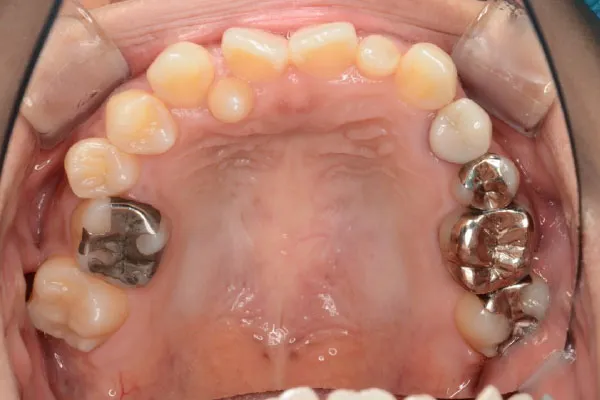

【40代女性】

反対咬合と内側の歯を

インビザライン矯正で

治療したケース

治療前

| 主訴 | 反対咬合 内側に歯がある |

|---|---|

| 期間 | 2年 |

| 費用 | 220,000円〜660,000円 (デンタルローン 3,100〜6,600円/月) |

| 治療内容 | インザライン矯正 非抜歯 |

| 治療に伴うリスク | 矯正終了後は、リテーナーを指示通りに使用し、歯の後戻りを防ぐ必要があります。 |